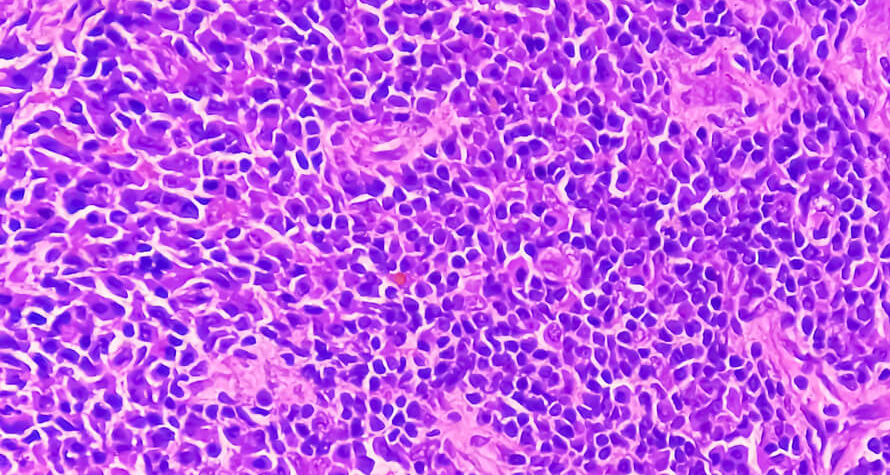

Image Description